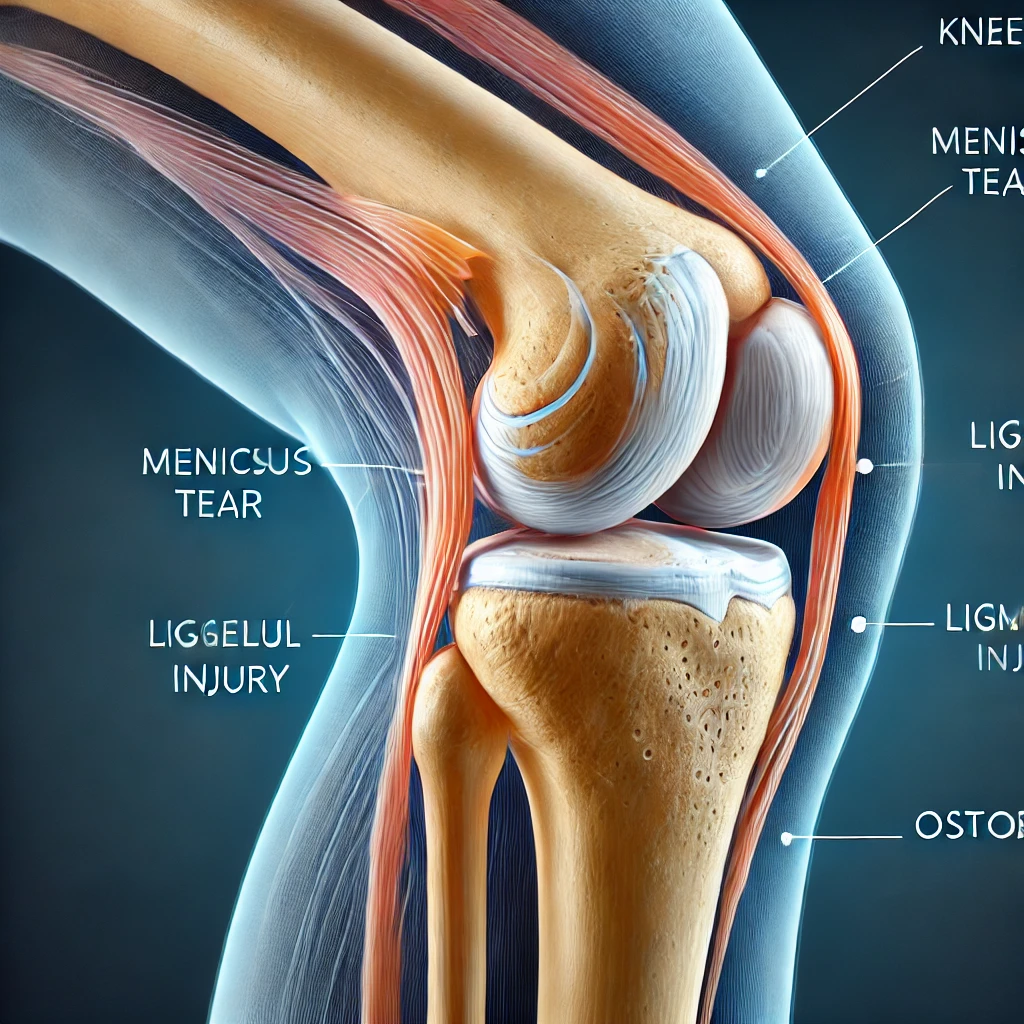

Questo ambito comprende numerose condizioni dell’apparato muscolo-scheletrico. In molti casi la chirurgia ortopedica permette di recuperare movimento e di attenuare il dolore. Il percorso viene personalizzato in base a diagnosi, età, attività e obiettivi del paziente.

4. Condizioni trattate con chirurgia ortopedica

- Fratture e traumatismi.

- Malattie degenerative (es. artrosi).